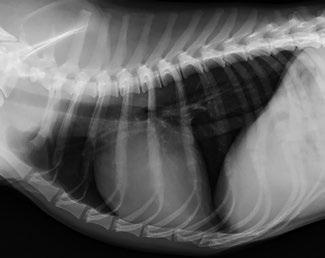

Issuu converts static files into: digital portfolios, online yearbooks, online catalogs, digital photo albums and more. Sign up and create your flipbook.